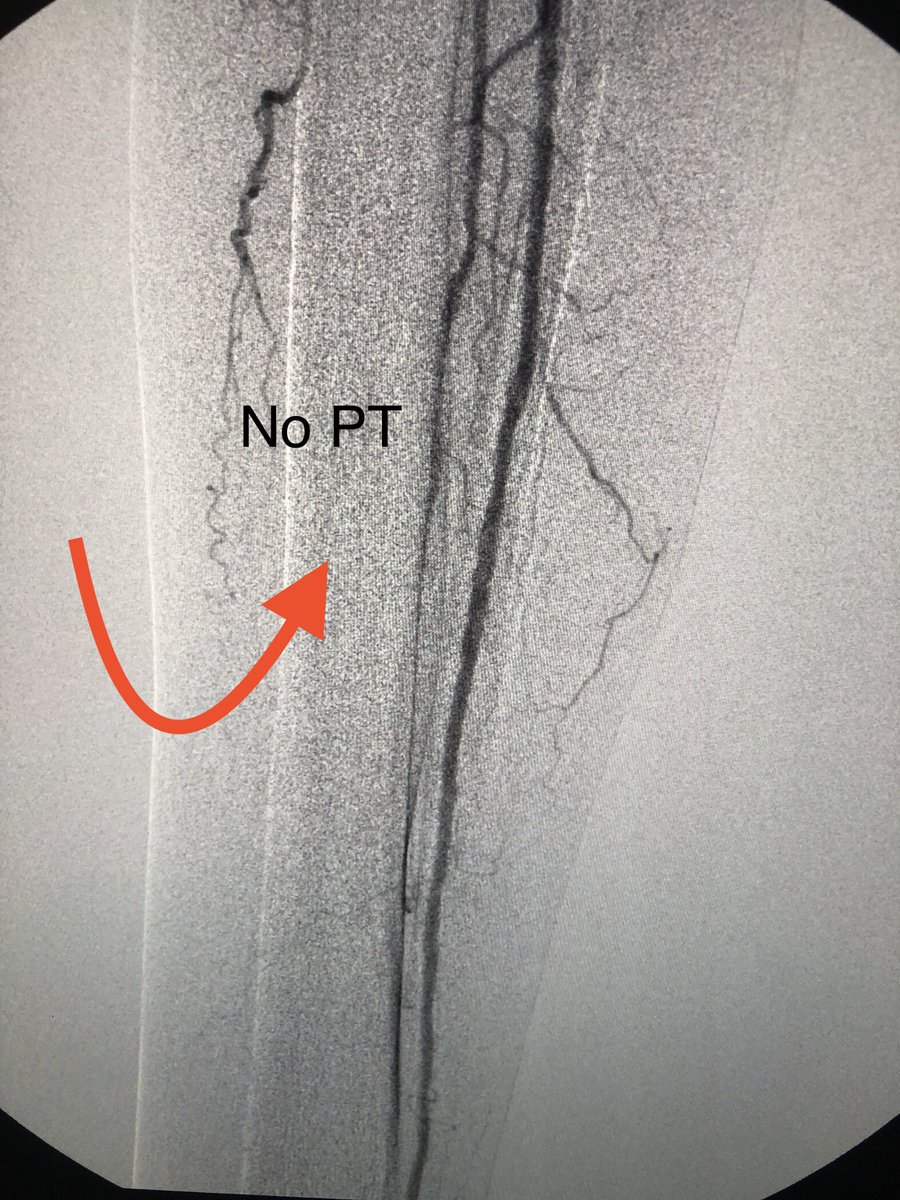

First look at Tigereye ..... 1000 rpm in single direction, deflectable tip, exchangeable support cath. I used the deflecting tip to precisely re-entry true lumen. Alot to learn to harness the power of #tigereye but gr8 start @AvingerInc